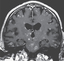

• IMAGE CHALLENGE

What is the diagnosis?